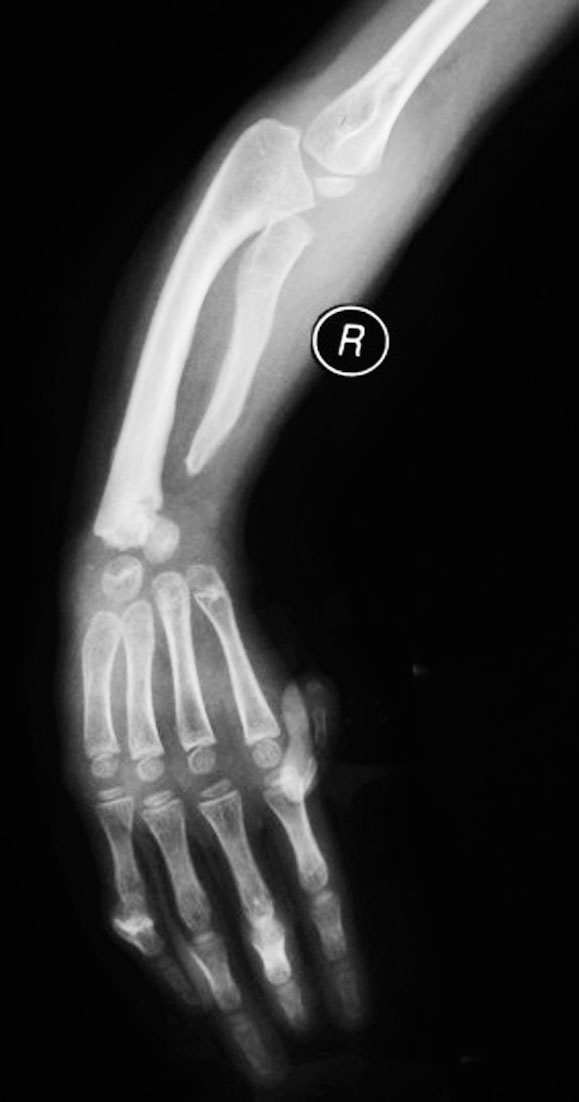

7.先天性缺掌(图1-2-1)。

图1-2-1 先天性缺掌病例

A.右手掌以远缺如;B.X 线片显示腕关节以远骨关节结构未发育(也可能为腕缺如)